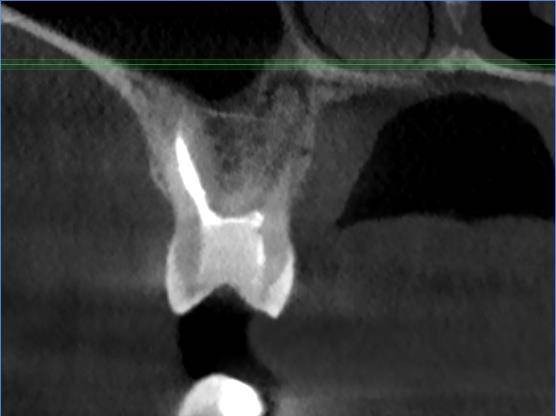

Есть зуб 11 (с СВШ) с восспалением около корня. До брекетов тоже было.

Перед протезированием предлагают перелечить каналы через корень с извлечением СВШ и последующим восстановлением (не понятно правда с СВШ или уже без него. Без СВШ зуб прям под корень может обломаться) под коронку.

До этого предлагали резекцию. Как в итоге лучше, через корень или резекцию?11-2.jpg.ba542aa82cfd6ddaad3fb9e234b99d99.jpg11.jpg.a34f40916e8e638d622001c50fff6e3a.jpg11-3.jpg.7a281f5893f8e6440937071fda10d523.jpg11-4.jpg.6a62c56e00cfdfa00cf35b7e276fd908.jpg